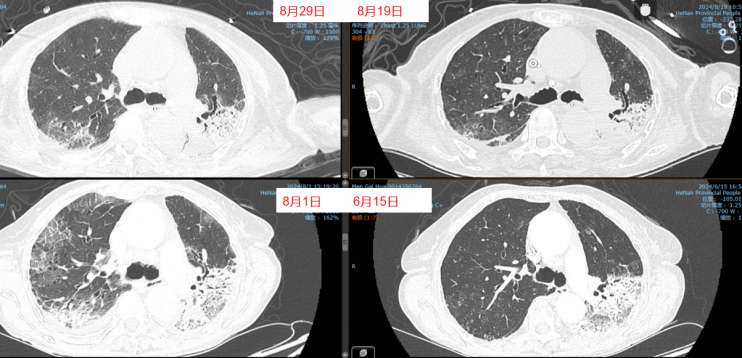

- 胸部CT(2024-06-13):左肺舌段和左下叶斑片实变影,右肺下叶可见斑片状阴影,肺中叶散在病变(图1)。

8月11日呼吸机吸氧浓度40%,ECMO气浓度约为80%,持续3天,激素减量氧合恶化,因心脏问题不能俯卧位通气(心率快,应用艾司洛尔及胺碘酮控制心室率)。气道分泌物不多,炎症指标正常。心脏问题,快速性心律失常,请心内科专家会诊,考虑舒张功能障碍,建议盐酸地尔硫卓联合胺碘酮控制心室率,血压低考虑可能血管张力问题,为减轻去甲肾上腺素对心脏的刺激,调整间羟胺维持血压。6月26日用抗肿瘤靶向药物后,8月1日肺部CT,双肺病变明显加重,肿瘤进展还是感染诱发?或是肿瘤靶向药物引起的免疫相关性肺损伤?下一步怎么办?肿瘤靶向药物还能用吗?8月11日请詹庆元教授会诊,考虑肿瘤靶向药物引起间质性肺炎可能性大,甲强龙80 mg q12h;心内科建议倍他乐克6.25 mg q12h口服联合盐酸地尔硫卓控制心室率;间羟胺替换去甲肾上腺素。8月12日心率65~85次/分,俯卧位8小时,白天ECMO 80%下调60%。患者氧合持续好转,随着病情好转,抗生素降阶梯治疗。8月13日,BALF涂片发现大量白细胞,以及多种形态阴性杆菌,像洋葱伯克霍尔德菌和伊丽莎白菌。8月14日,tNGS结果回报按蚊伊丽莎白菌、洋葱伯克霍尔德菌和脓肿分枝杆菌。据此调整抗感染药物:磺胺2片tid,多黏菌素E,美罗培南,利奈唑胺,伏立康唑。8月20日撤离ECMO。8月21日,病原学提示脓肿分枝杆菌进行性增多,加用左氧氟沙星。8月26-28日尝试甲强龙减量(60 mg→40 mg),患者再次再次出现氧合变化,未能成功转换为无创通气,有创通气PS降至8 cmH2O,PEEP 5 cmH2O。复查胸部CT,发现右肺渗出性病变再次出现。8月29-30日,甲强龙剂量调整为80 mg。8月31至9月3日,甲强龙剂量调整为60 mg。8月27日复测tNGS,回报木糖氧化无色杆菌(序列数47605),人类疱疹病毒1型(序列数176998),按蚊伊丽莎白菌、洋葱伯克霍尔德菌和脓肿分枝杆菌序列数较前减少。细菌室回报木糖氧化无色杆菌。患者出现了一些不良反应,包括骨髓抑制,纤维蛋白原、血小板、血红蛋白、白细胞、淋巴细胞数都在降低。考虑可能是磺胺药物和利奈唑胺引起,所以停用这两种药物。调整抗感染药物:阿米卡星雾化,左氧氟沙星,多西环素,伏立康唑,阿昔洛韦。之后由于不良反应,8月31日停用了左氧氟沙星和多西环素。9月3日查血,患者血小板升高。如下图所示,6月15日为抗肿瘤药物使用前,8月1日为抗肿瘤药物使用后,8月19日第一次复查CT,激素减量后,8月29日再次复查CT,右肺渗出性病变较前明显增多(图4)。

图4 患者影像学变化